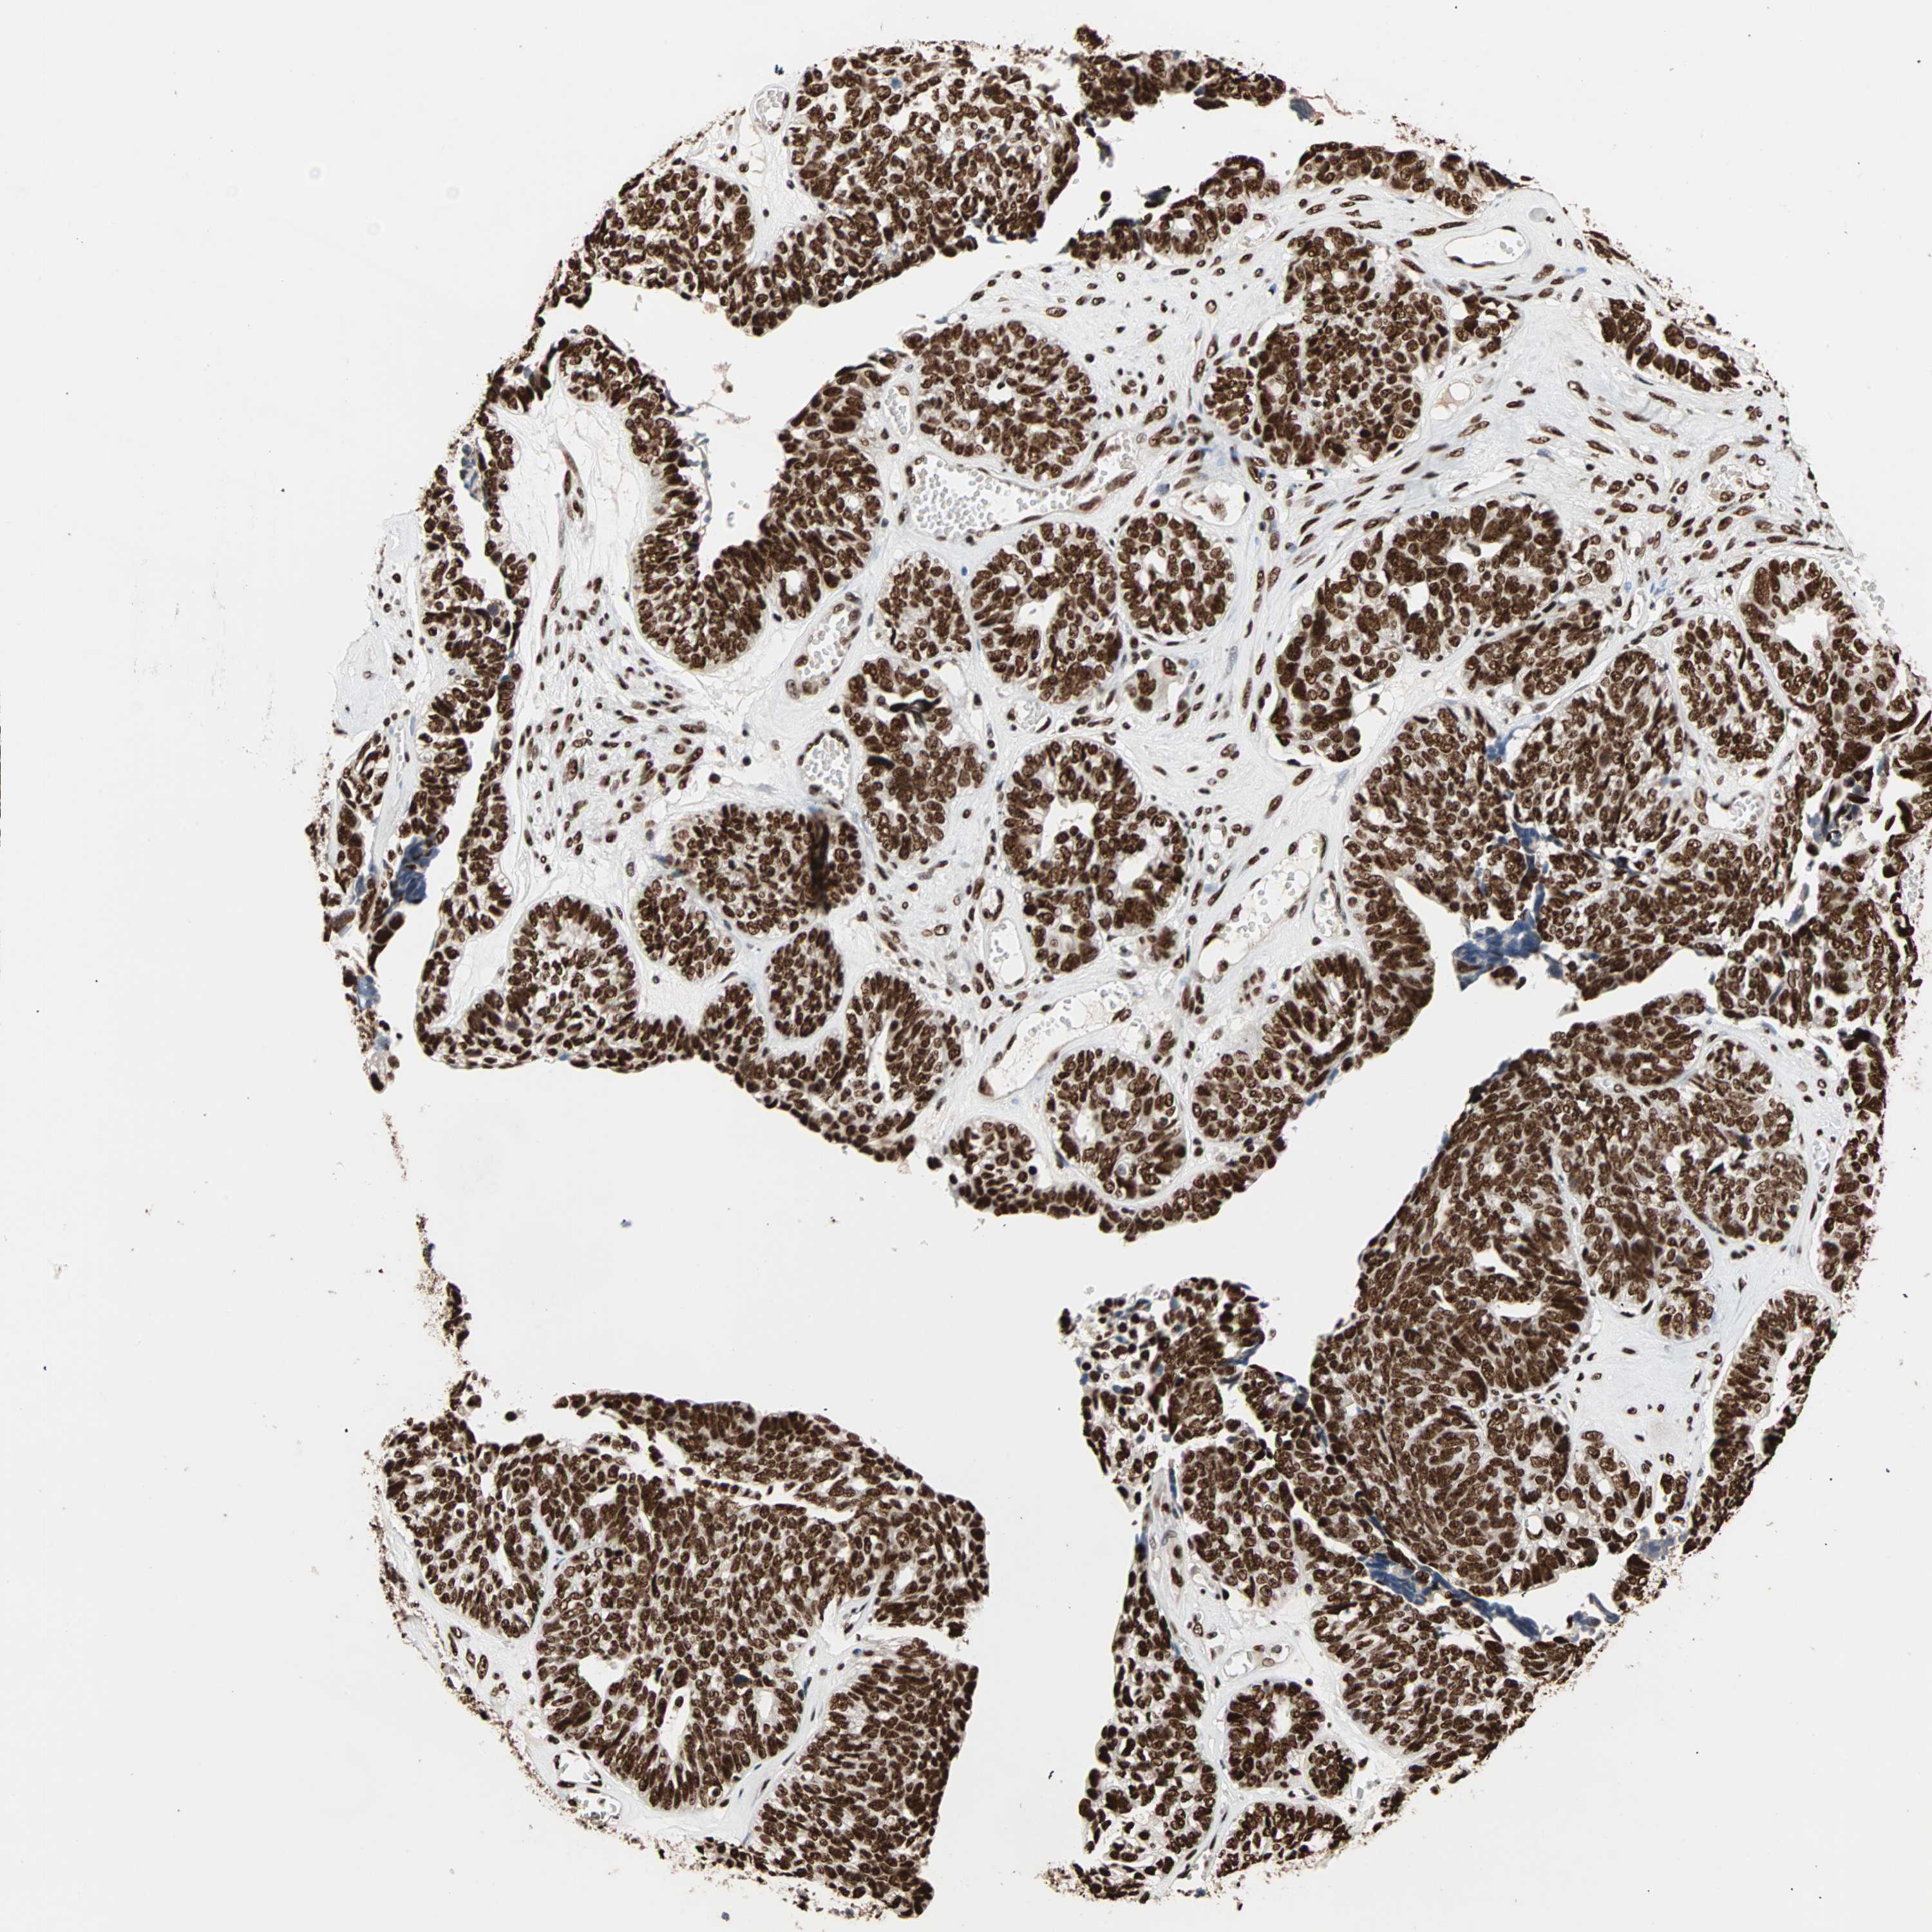

OVARIAN CANCER - Protein expressioni

A mouse-over function shows sample information and annotation data. Click on an image to view it in a full screen mode. Samples can be filtered based on level of antibody staining by selecting one or several of the following categories: high, medium, low and not detected. The assay and annotation is described here.

Note that samples used for immunohistochemistry by the Human Protein Atlas do not correspond to samples in the TCGA dataset.

Antibody stainingi

Antibody staining in the annotated cell types in the current human tissue is reported as not detected, low, medium, or high, based on conventional immunohistochemistry profiling in selected tissues. This score is based on the combination of the staining intensity and fraction of stained cells.

Each image is clickable and will lead to virtual microscopy that enables deeper exploration of all samples and also displays staining intensity scores, fraction scores and subcellular localization as well as patient and tissue information for each sample.

Antibody HPA007484

Staining

High

Medium

Low

Not detected

Intensity

Strong

Moderate

Weak

Negative

Quantity

>75%

75%-25%

<25%

None

Location

Nuclear

Cytoplasmic/membranous

Cytoplasmic/membranous,nuclear

Cystadenocarcinoma, serous, NOS

Carcinoma, endometroid

Cystadenocarcinoma, mucinous, NOS

Carcinoma, NOS